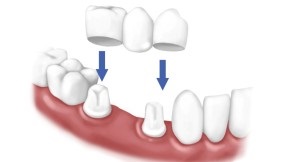

În imagine stampilat coroanele

Diferite tipuri de coroane și cum să le instalați: